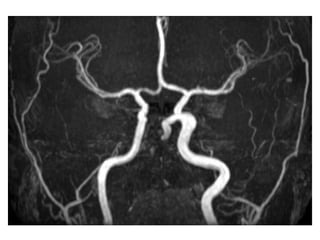

MRA with non-visualization of the left transverse sinus, since the venous anatomy is

variable, this can be due to absence of the transverse sinus or thrombosis, the T1

clearly demonstrates, that there is a transverse sinus on the left, so the MRA

findings are due to thrombosis